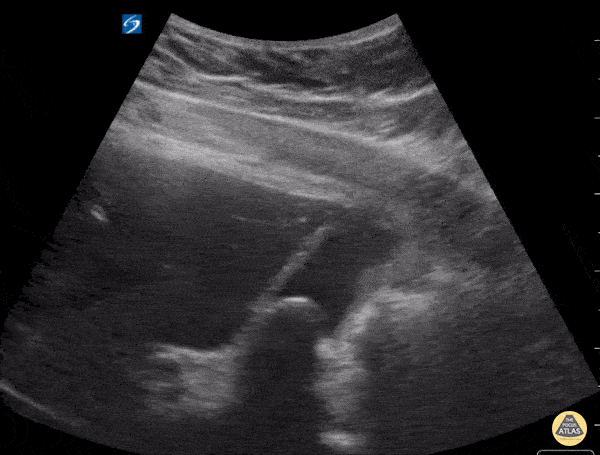

14 year old patient found to have large gallstone. Shown here is long axis view of the gallbladder, notice the shadowing present from the gallstone as the probe is fanned. Kathryn Pade, MD